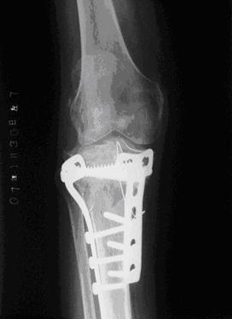

为了防止对胫骨平台骨折手术后延迟负重导致的骨折延迟愈合、关节僵直、肌肉萎缩、骨质疏松等并发症。我们在临床应用气压减重训练仪,采取早期个性化定量的减重负重训练治疗累及关节面的胫骨平台骨折。通过治疗取得良好疗效,患者的骨折愈合良好而没有出现关节面的塌陷,关节功能恢复正常(图1-3)。

图1.一例左膝胫骨平台骨折 图2.内固定术后的X线片表现